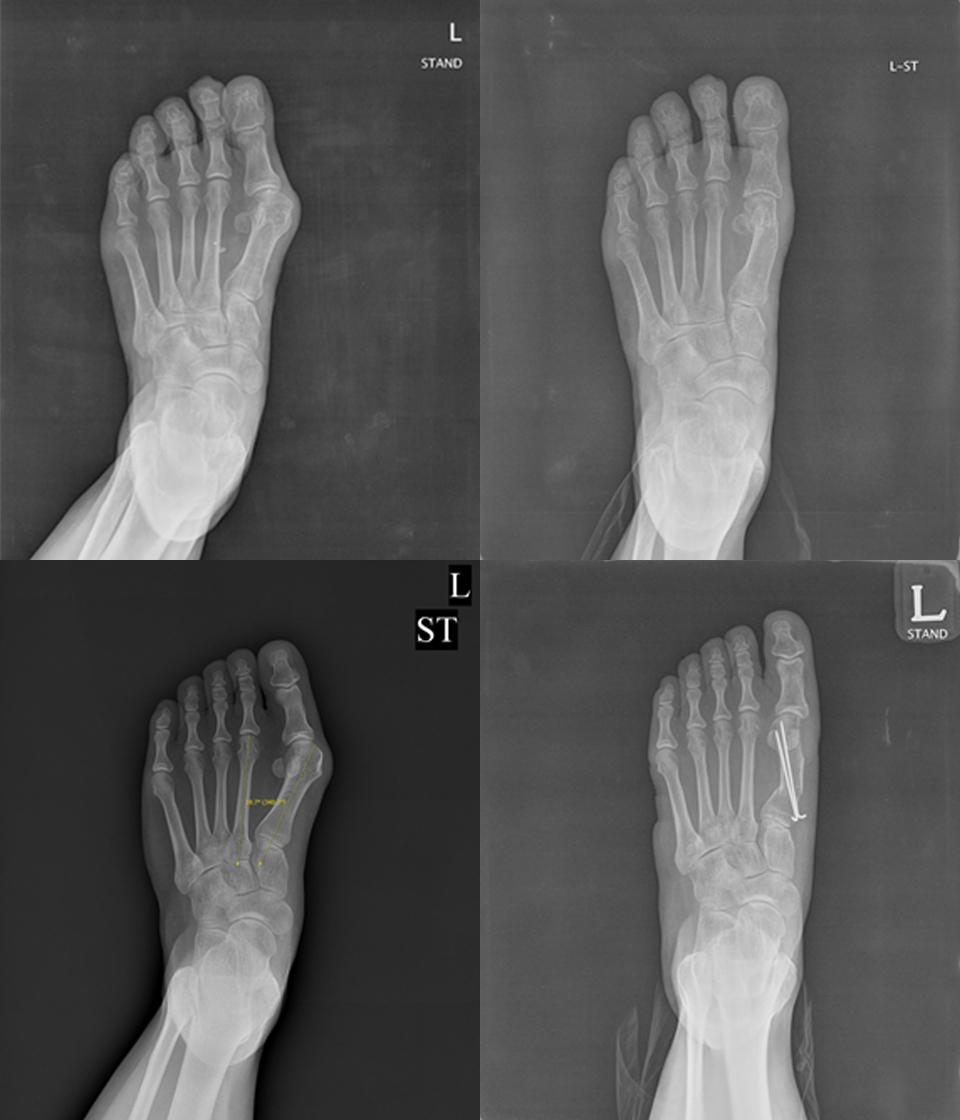

Hallux valgus

무지외반증

무지외반증 이란

무지에 발생하는 가장 흔한 질환으로,

무지가 외측으로 휘어 제1중족 족지 관절이 안쪽으로

돌출되어 통증 및 염증을 유발하며 발이 변형됩니다.

3. 수술치료

• 원위 연부조직

유리술

• 원위 갈매기

절골술

• 근위 갈매기

• 유합술

- 환자 동의하에 게시된 이미지입니다.